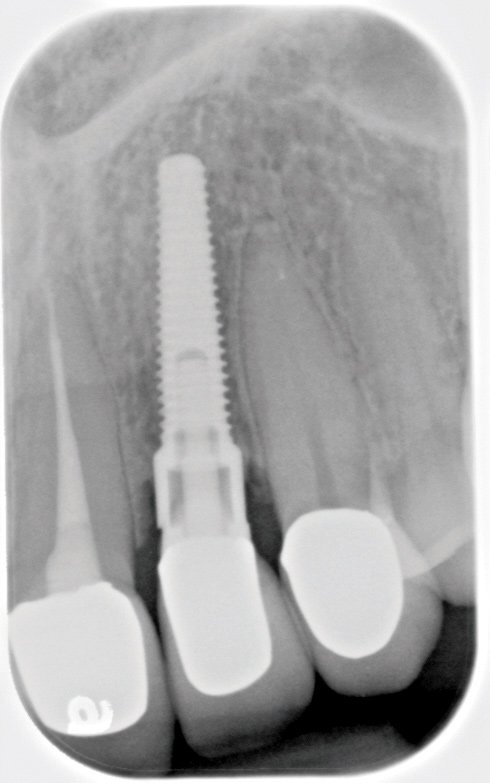

Fig 13. Radiograph depicting peri-implantitis.

Figure 13